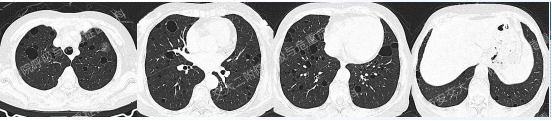

上述3个病例均为弥漫性囊性肺疾病,鉴别至关重要。

温故知新

以下2例不同患者的胸部影像改变,又分别考虑什么疾病呢?